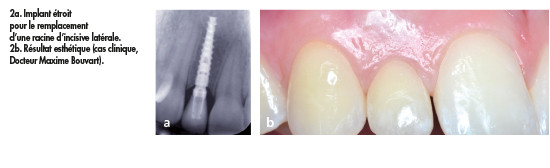

Choisir un implant de petit diamètre permettra une meilleure angiogenèse et cela améliorera le score papillaire en secteur esthétique (fig. 2).

En effet, contrairement à la dent qui reçoit également sa vascularisation du desmodonte, la gencive péri-implantaire n’est vascularisée que par le périoste. Cette hypo-vascularisation est à l’origine d’une défense antibactérienne moins efficace, et d’une perte des papilles.